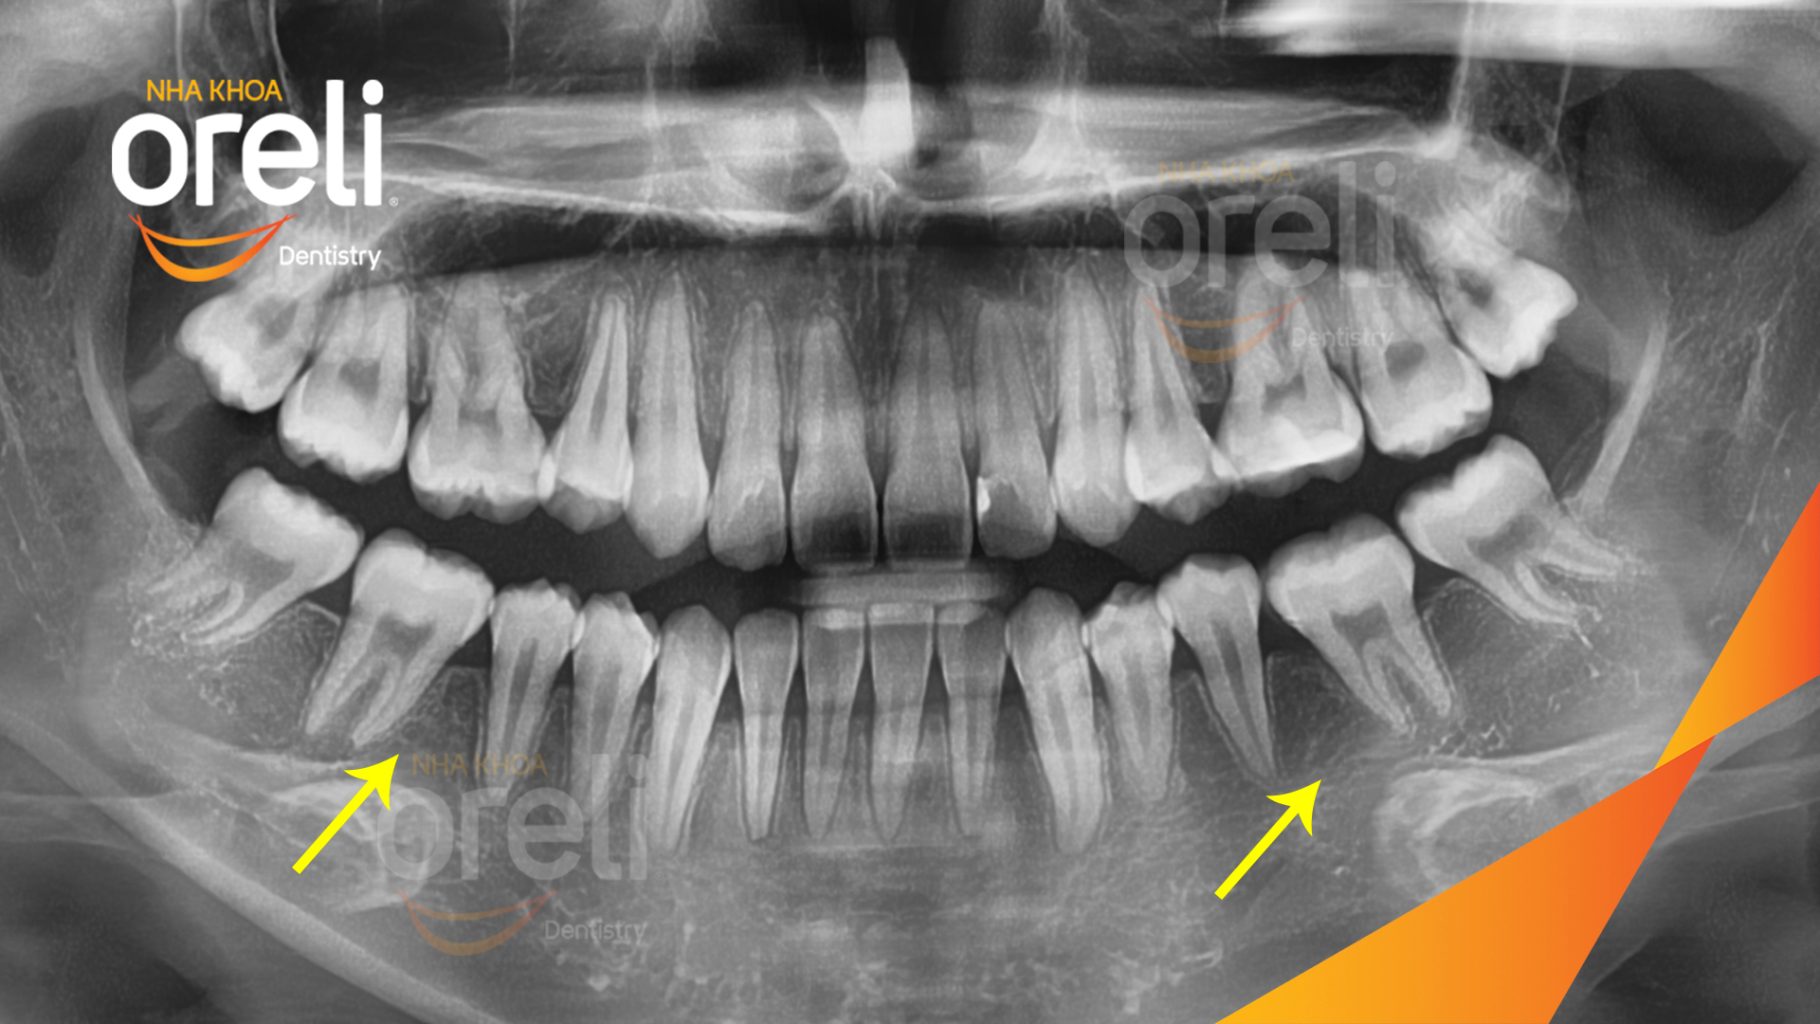

Ca niềng chỉnh hô nhổ 2 răng 4 hàm trên di gần răng 7 8 hàm dưới cho nụ cười đẹp – Kết quả sau hơn 2 năm ở Oreli

Ca niềng răng di gần răng 7 8 phục hồi ăn nhai và thẩm mỹ nụ cười. Kết quả thực tế trước và sau điều trị tại Nha khoa Oreli.

NIỀNG RĂNG HÔ KÈM DI GẦN RĂNG HÀM Ở NHA KHOA ORELI